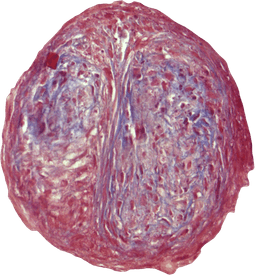

VitroScreen, a SenzaGen Group company, pioneers next-generation in vitro testing solutions. We leverage cutting-edge biological models—from 2D cells and reconstructed tissues to ex vivo systems and cellular spheroids—to deliver precise, human-relevant data for the Cosmetics, Medical devices, Nutraceuticals, Pharma and Chemicals industries.

Our models mirror human biology for precise, predictive accuracy.

We design and execute rigorous preclinical in vitro studies, combining validated testing standards with fully customized protocols to deliver reproducible, decision-ready results. Our expertise covers multiple product categories and therapeutic areas, providing highly predictive platforms for both regulatory and efficacy assessment.